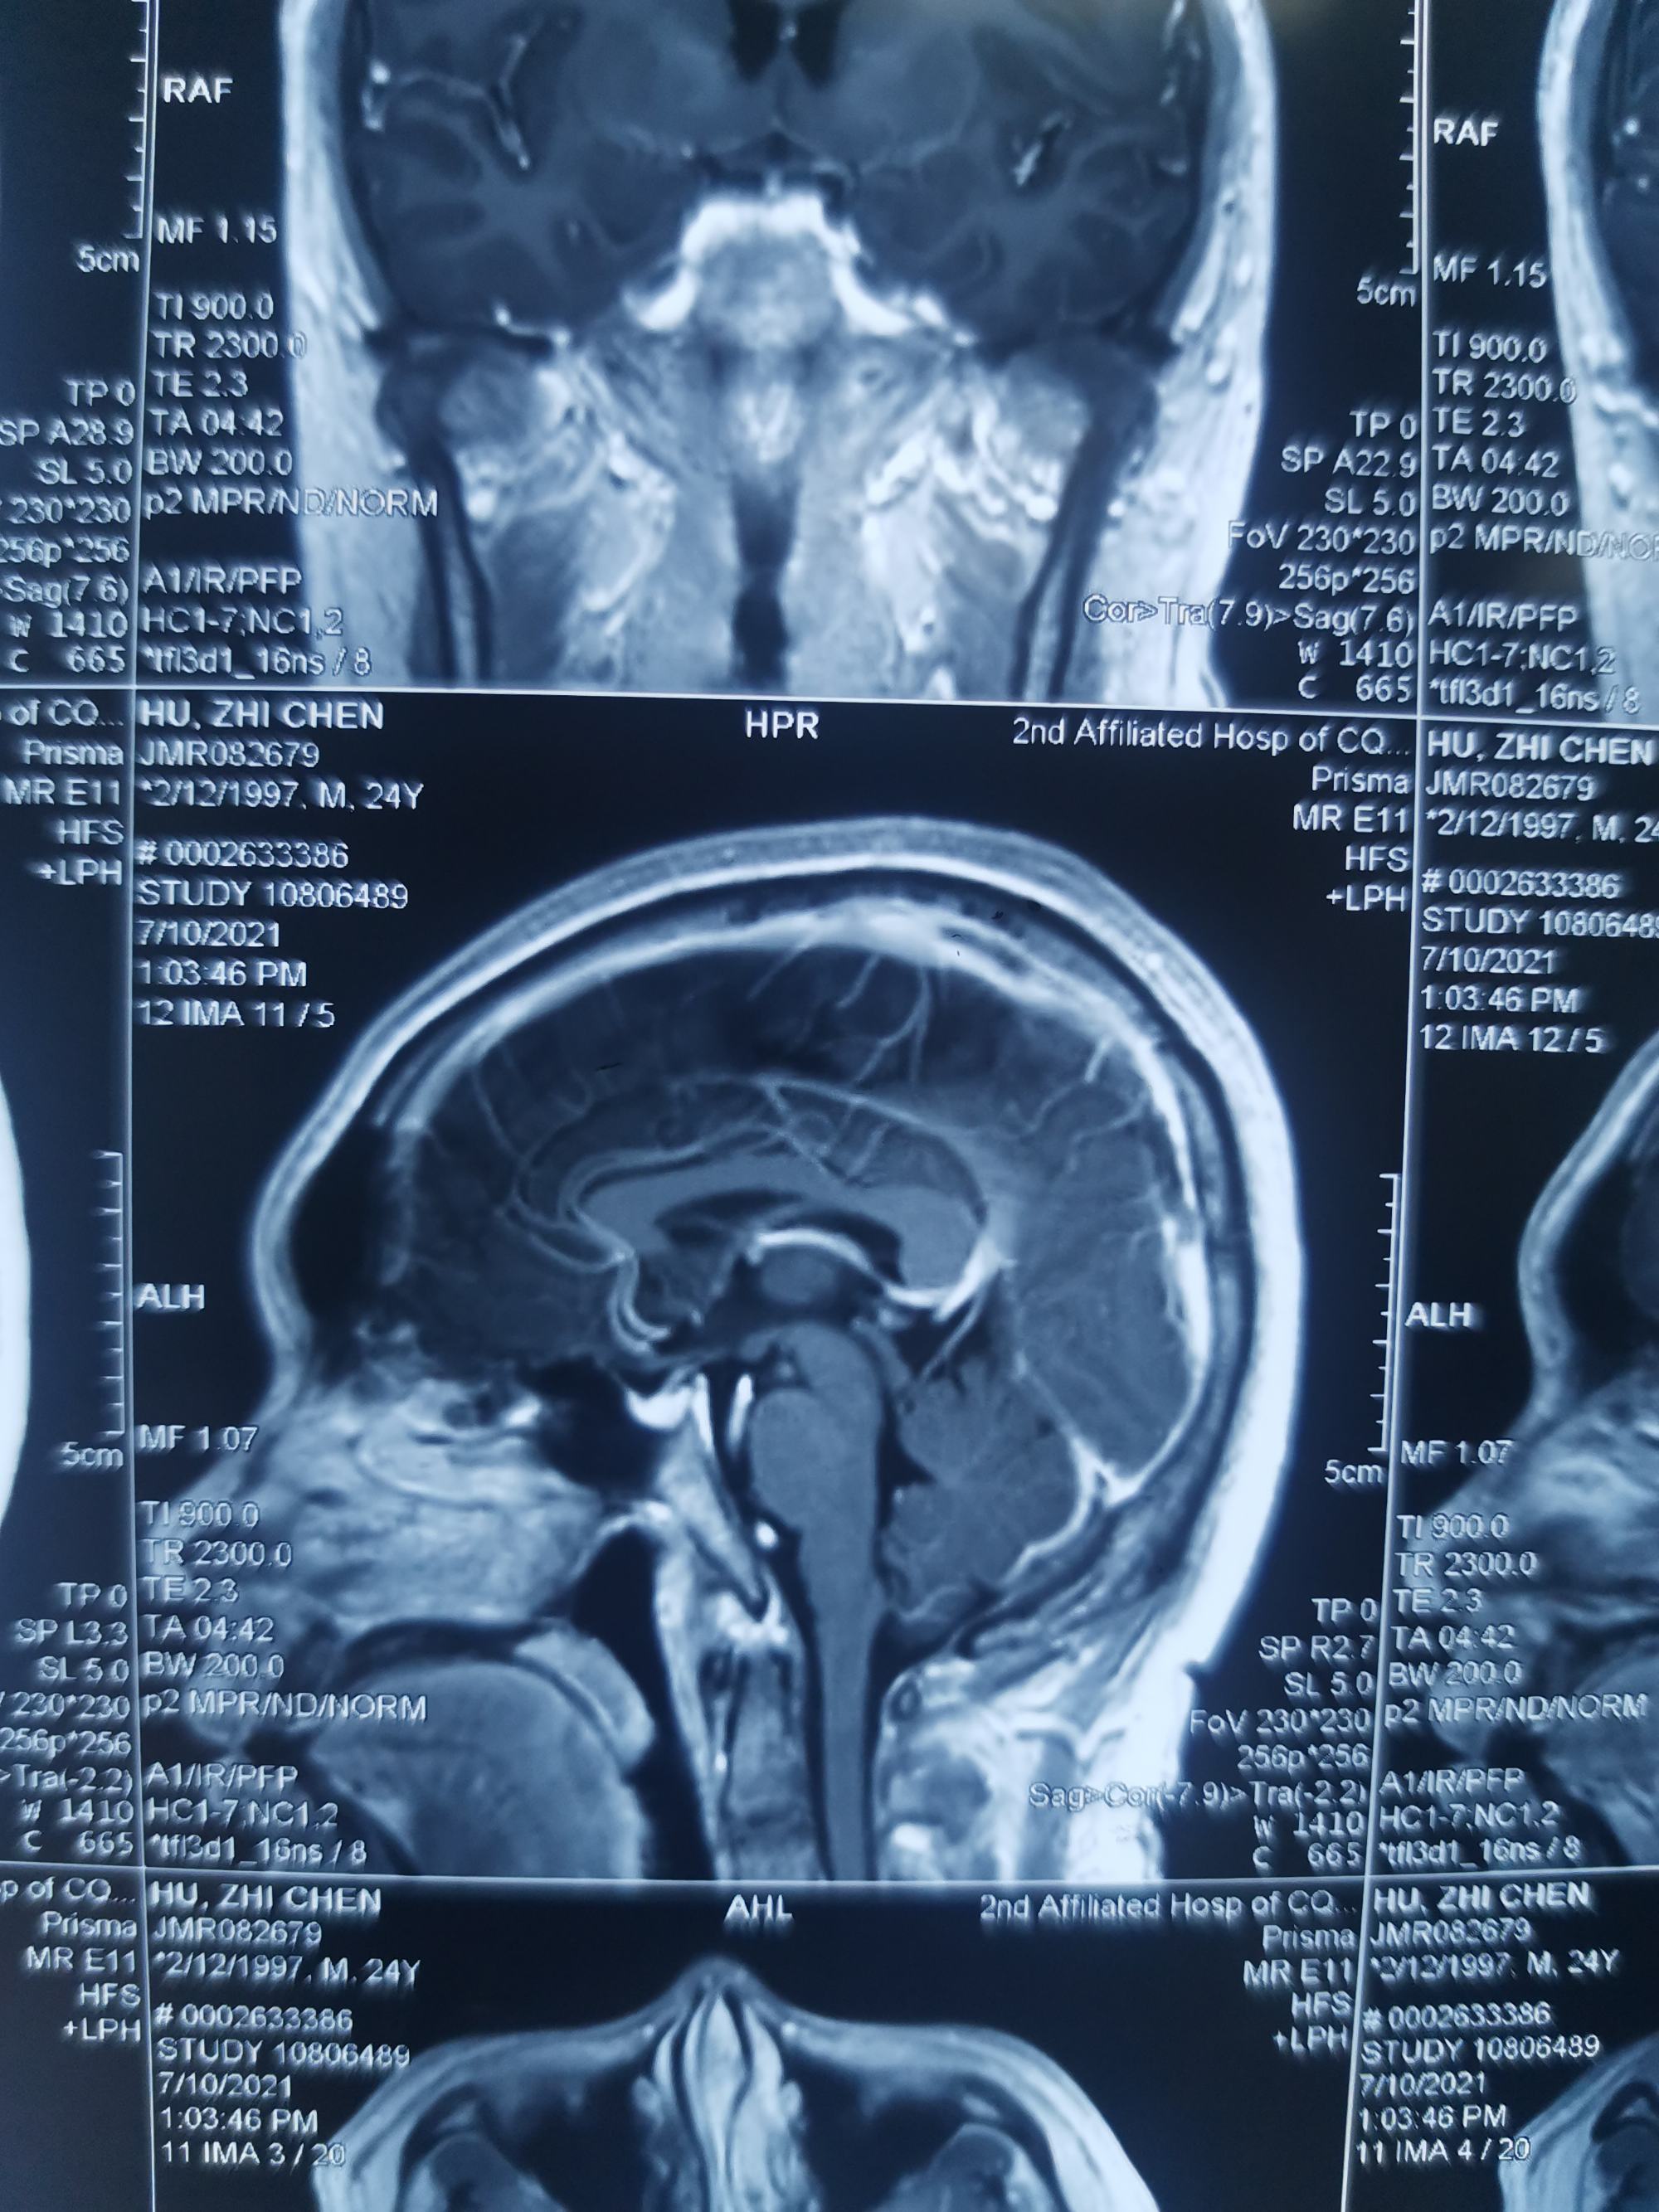

外院磁共振增强见,矢状窦局部充盈缺损。

增强显示矢状窦长节段充盈缺损,D-2聚体大于正常上限5倍以上。我科诊断考虑上矢状窦血栓形成伴多发多次脑梗死伴出血。

矢状窦全程血栓,与外院相比血栓明显扩大。立即急诊行脑血管造影+介入取栓术。

矢状窦是大脑最大的回流静脉,相当于颅内的长江,长江主干闭塞,各支流必将洪水泛滥。患者随时可能再发脑梗和脑出血可能。立即急诊行脑血管造影+介入取栓术。

患者左侧横窦优势,左侧颈内动脉造影侧位见矢状窦起始部至横窦水平未显影。